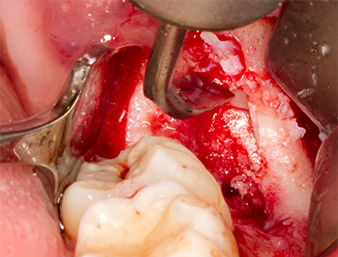

Um autogenes Material für die spätere Wundversorgung zu gewinnen, wurden mit einem piezochirugischen Instrument (Piezomed B5) gesunde Knochenspäne aus der Umgebung des Wurzelrests gewonnen (Abb. 5).

Das autogene Gewebe wurde mit dem schaufelförmigen Arbeitsteil des Instruments entnommen und bis zur weiteren Verwendung in physiologischer Kochsalzlösung aufbewahrt (vgl. Abb. 13).

Um den Wurzelrest gewebeschonend frei zu präparieren, kam ein weiteres Instrument zum Einsatz (Piezomed S2), das primär für die Präparation des lateralen Fensters bei Sinusboden-Augmentationen indiziert ist. Zusätzlich wurden mit der diamantierten Kugel scharfe Knochenkanten geglättet (Abb. 6 und 7). Alle eingesetzten Piezomed-Aufsätze arbeiteten mit der jeweiligen automatischen Standardeinstellung ohne Booster-Funktion.